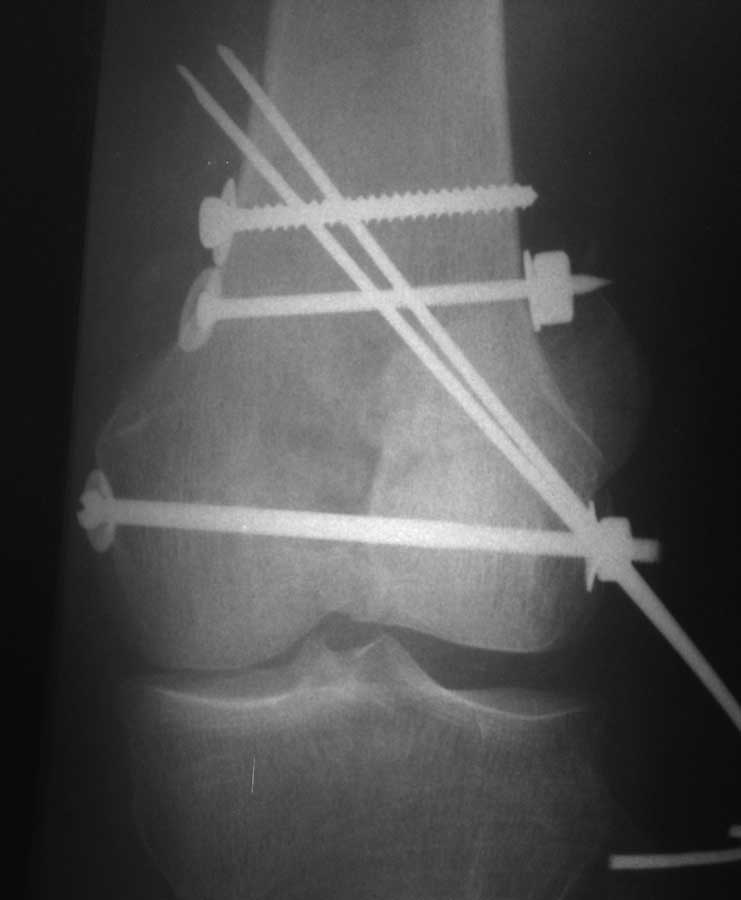

Коллеги, извиняюсь за задержку с результатом. Через медиальную артротомию обнажили н/3 бедра, отрепонировали внутренний мыщелок, затем по нему сопоставили суставную поверхность бедра с латеральным мыщелком.

Больная выписана в ортезе с регулируемым углом сгибания в колене, с рекомендациями через 3 нед. удалить спицы и начать разрабатывать сустав.

По прямому снимку репозиция удалось, поздравляю! А с латеральной стороны подозрение на флексионный компонент латерального мыщелка остается, а снимок получился косым, надо было бы повторить.

Выбор имплантов не совсем удачный, подкожно выступающие болты в мыщелках вскоре могут привести к проблемам. Вместо солитарной фиксации болтом-стяжкой дистально можно было бы добавить пару винтов, которые создали бы ротационную стабильность и межфрагментарную компрессию.

Возможно, есть скрытый замысел, неочевидный для нас - не понятны латерально оставленные спицы. Спицы возможный очаг вторичного осложнения, и, тем более у взрослых, тонкие спицы не создают адекватную фиксацию.

Djoldas,скрытого смысла в спицах нет. Без них латеральный мыщелок получается фиксированным только к медиальному, который, в свою очередь, фиксирован к проксимальному отломку. Соответственно латеральный мыщелок не фиксирован к бедру. Спицами мы попытались создать какую-никакую-стабильность латерального мыщелка относительно проксимального отломка бедра.

Болт-стяжка, на мой взгляд, создает не меньшую межфрагментарную компрессию чем винты. Не понял относительно ротационной стабильности винтов.